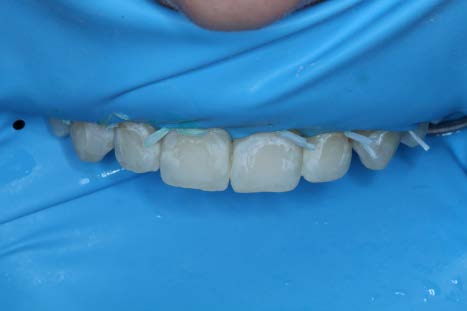

After a second 2 minute application of HCl etch, the Icon Dry alcohol solution was applied to check for visual improvement (not pictured). Most lesions appeared camouflaged at this point other than teeth #7 and #11. So a third round of etching was performed.

After the third round of etching, Icon Dry was applied and the lesions were almost completely camouflaged. Note that in the picture the lesions appear worse than original when dry, however, when the Icon Dry alcohol or resin Infiltrant are applied, the color improves drastically.